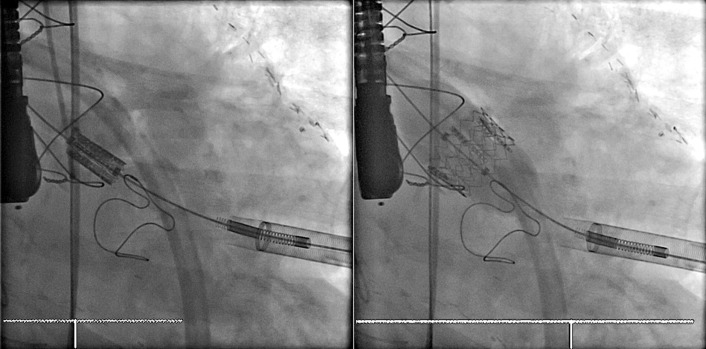

Percutaneous/transcatheter heart valves are constructed of either bovine jugular venous valves that are suspended on wire mesh cages (Bonhoeffer design/Melody Transcatheter Pulmonary Valve–TPV, Medtronic), or consist of a valve created from bovine pericardial tissue that is suspended on wire mesh cages (Edwards Sapien and Medtronic CoreValve). Percutaneous aortic valve implantation is currently one of the most rapidly proliferating percutaneous interventions in the world ( Figs. 13-11 to 13-13 ).

Thoracic aortic stenting/endografting is increasingly performed as treatment of coarctation of the aorta, aneurysm of the thoracic aorta, false aneurysm of the thoracic aorta, penetrating ulcers, and dissections ( Table 13-2 ). Thoracic aortic stenting may employ either uncovered or (ePTFE)-covered stents, depending on the nature of the lesion and the desired intervention. The supportive wire network of aortic stents is readily visible on chest radiography. FLOAT NOT FOUND FLOAT NOT FOUND FLOAT NOT FOUND FLOAT NOT FOUND FLOAT NOT FOUND FLOAT NOT FOUND FLOAT NOT FOUND FLOAT NOT FOUND FLOAT NOT FOUND FLOAT NOT FOUND